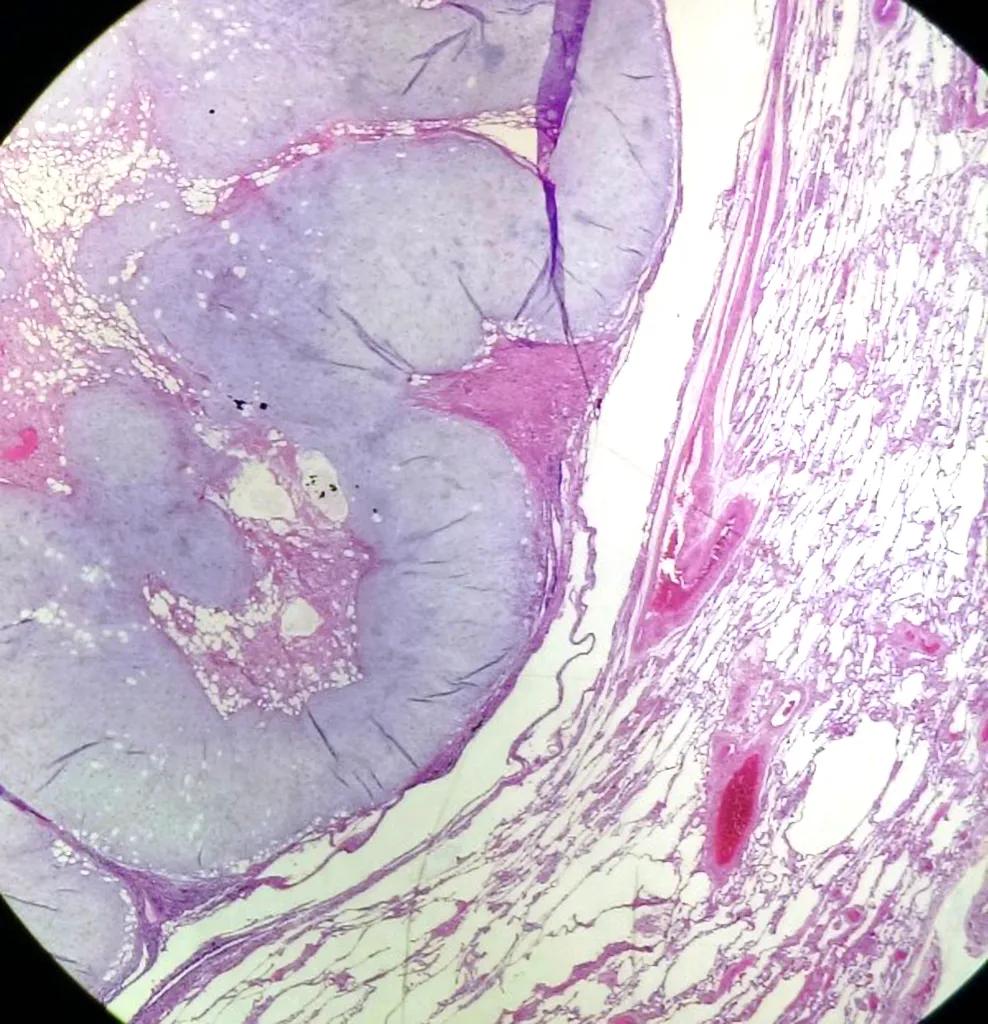

病理大体标本

镜下组织细胞

20x H&E: 病变是实性的,与周围的实质清晰地划定。

在低功率下,可以欣赏到软骨和脂肪组织的混合物。